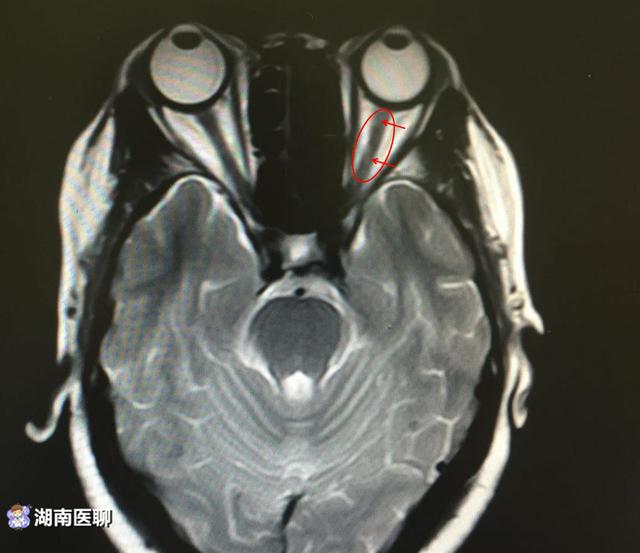

(脊髓横截面脊髓前部异常信号)

发现高位颈髓出现明显异常信号,并且患者右侧存在视神经异常信号。

(左侧视神经异常信号提示视神经受累)